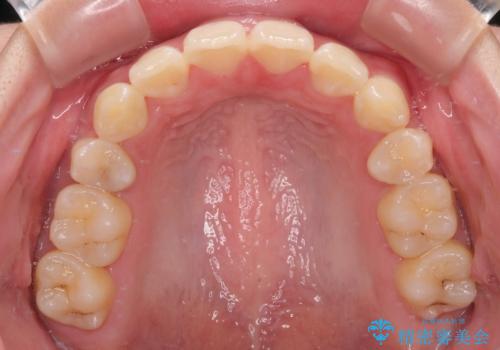

口元が出ているのを改善したい。 クリアブラケットによる抜歯矯正

舌突出癖を改善するトレーニングを一生懸命やっていただいたおかげで2年以内に治療を終えることができました。

- 前歯部のデコボコと口元が出ているのが気になるとのことで来院された患者様です。

口元の突出感の解消と、このままデコボコを解消するとさらに出っ歯傾向になってしまうことを考慮し、上下左右の小臼歯を抜歯しクリアブラケットにて矯正していくこととしました。